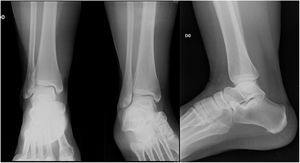

En el caso 4 se estableció el criterio quirúrgico la diferencia de 9 grados en el ángulo talocrural con la radiografia comparativa y el espacio claro medial aumentado 1mm.